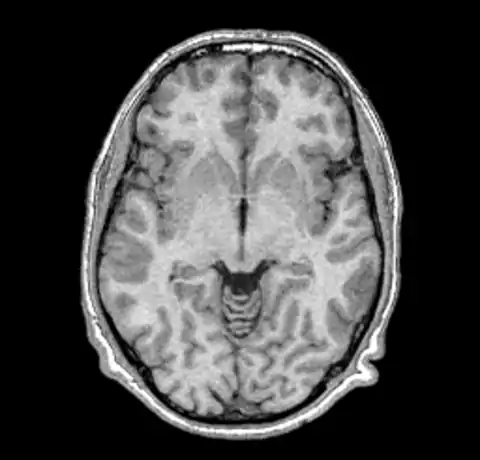

B0 non-uniformity is difficult to detect when simply looking at images without the assistance of a judiciously ranged color map. In our test case we'll start with a simple T1 MPRAGE image from a 1.5T Siemens scanner.

The above image and all the images here were created using mincpik in a similar fashion to the below.

mincpik -scale 2 original.mnc -slice 150 -image_range 10 80 original.png

Note that it is difficult to pick the non-uniformity in the image unless you look carefully at the intensity of the white matter in the lower parts of the image. In order to correct this image we run nu_correct with the default parameters.